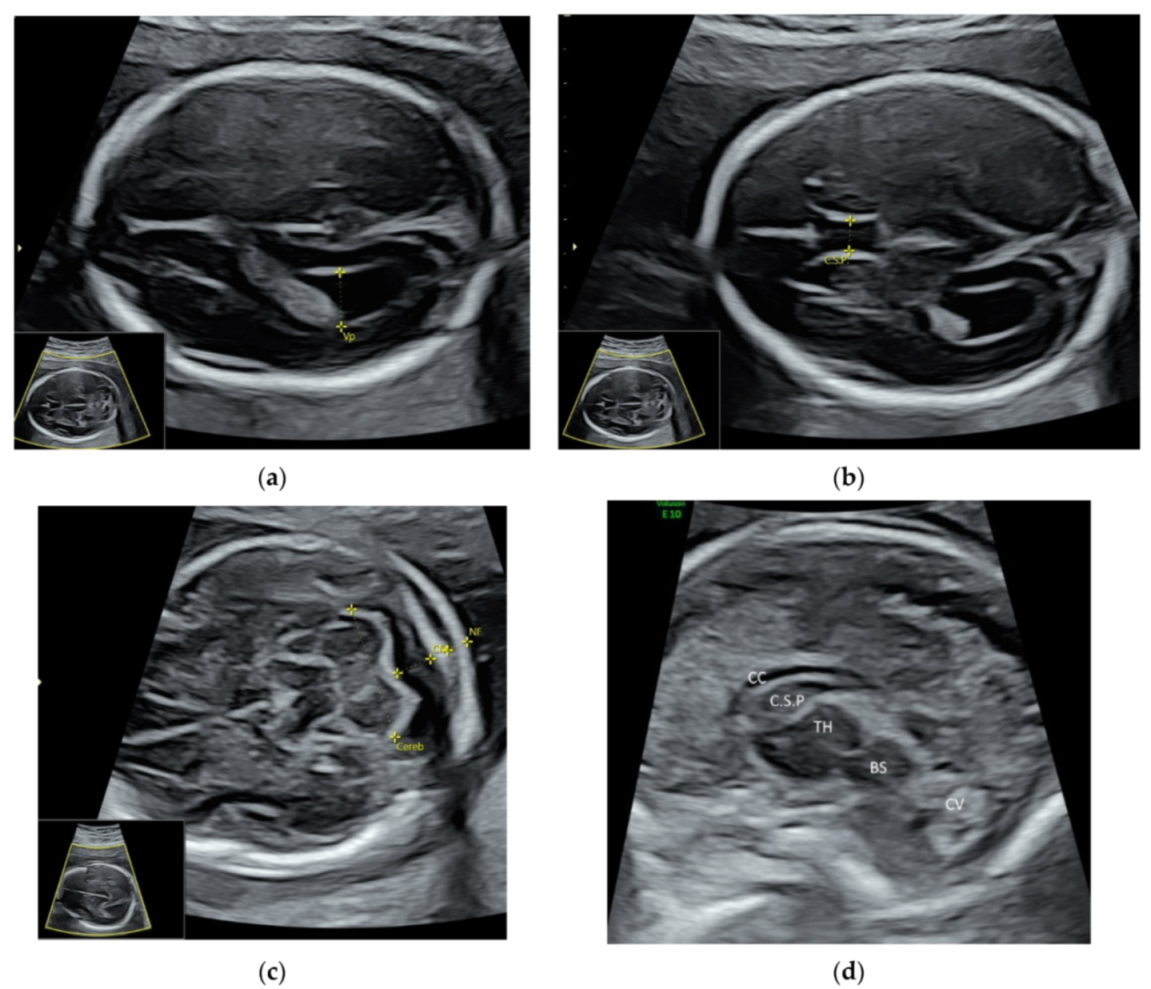

For a targeted neurosonographic examination, ISUOG recommends the use of high- resolution transvaginal transducers whenever possible [5]. An alternative is to use high-resolution transabdominal transducers with high frequency reaching 8–9 MHz [5]. The anatomy of the fetal brain is examined in details on a continuum of transverse, sagittal and coronal planes (Figure 2a–d, Video S2a,b).

Figure 2.

High-resolution ultrasonography of the fetal brain at 20 weeks’ gestation: transverse views showing (a) posterior horn of the lateral ventricle (Vp), (b) cavum septi pellucidi (C.S.P.), (c) cerebellum (Cereb), Cisterna magna (CM), nuchal fold (NF), and sagittal view showing (d) corpus callosum (CC), thalamus (TH), brain stem (BS), and cerebellar vermis (CV).